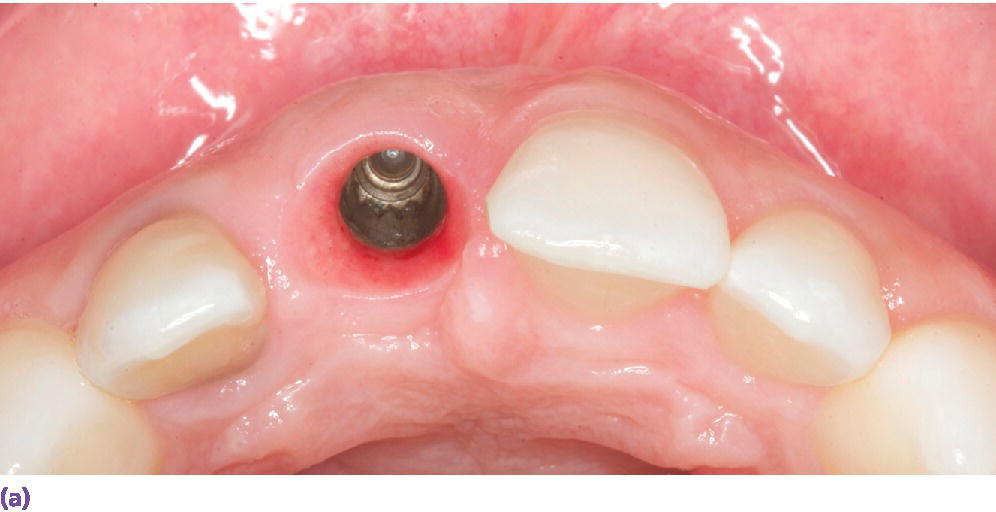

9 Esthetic anterior implant restorations Surgical techniques for Dental Implant Esthetic Zone Objectively, the esthetic zone was defined as any dentoalveolar segment that is visible upon. surgical placement of dental implants in the anterior zone requires careful treatment planning, particularly in terms of fixture selection. definition of the esthetic zone: Implant therapy in the aesthetic zone: immediate implant placement and provisionalization in the esthetic zone. immediate implant placement. Dental Implant Esthetic Zone.